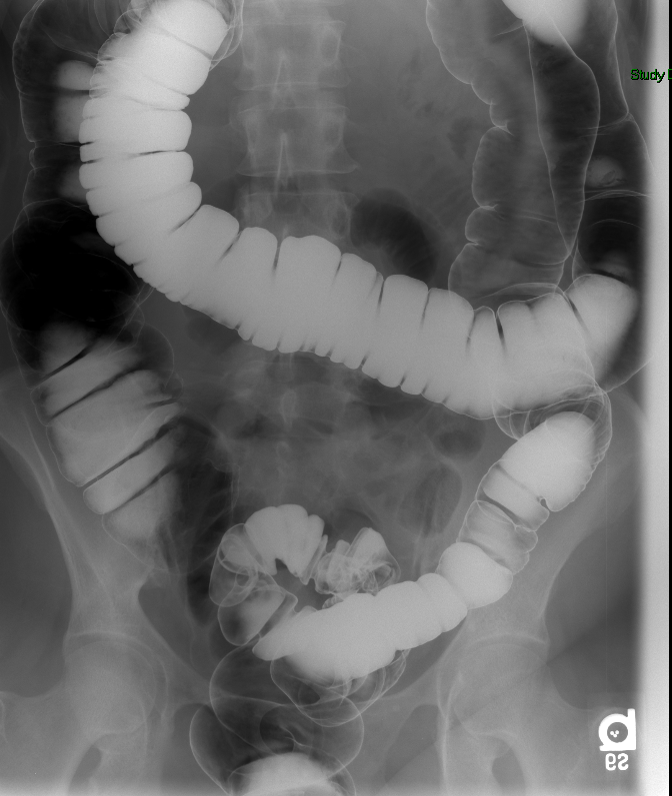

- The technologist will obtain post study overhead radiographs:

- PA to include the entire colon

(key image 8)

- PA angle (35 degrees caudal), patient positioned in slight RAO (~15 degrees), to include the rectosigmoid colon

(key image 9)

- RPO (~45 degrees), to include the splenic flexure

(key image 10)

- LPO (~45 degrees), to include the hepatic flexure

(key image 11)

- AP angle (35 degrees cephalad), patient positioned in slight LPO (~15 degrees), to include the rectosigmoid colon

(key image 12)